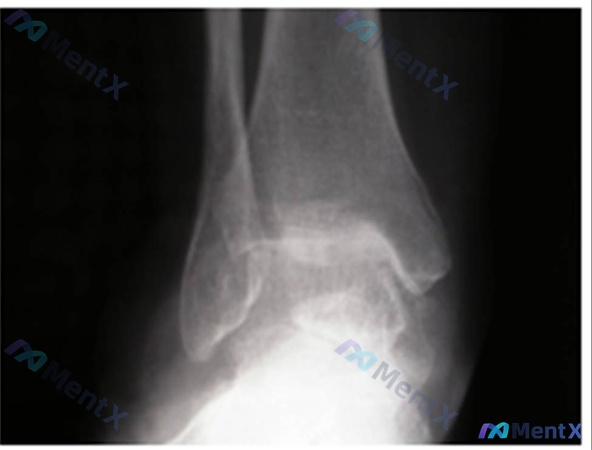

整理到一个有点意思的全踝置换术后病例,容易踩思维陷阱。 > 基本情况: > - 65岁男性,终末期踝关节炎 > - 术前接受过支具、理疗、NSAIDs,效果不佳 > - 行了全踝关节置换术(TAA),术中用了下胫腓联合横向螺钉 > - 术后10个月,仍持续疼痛、行走困难 > 目前检查: > - 手术...